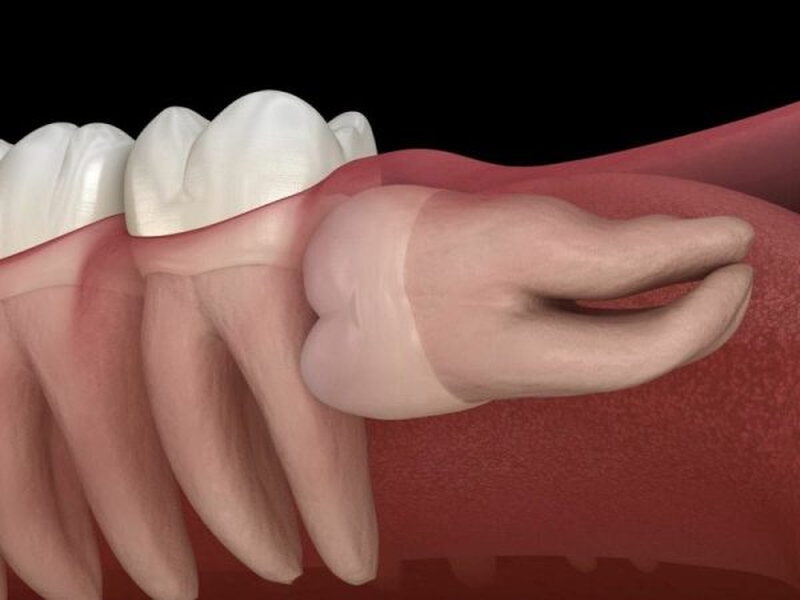

• Hầu hết răng khôn mọc ngầm đều được chỉ định nhổ bỏ. Điều này là bởi vì răng khôn mọc lệch lạc có thể gây nguy hiểm cho răng số 7, lâu ngày khiến cho răng số 7 lung lay và yếu đi.

• Răng mọc ngầm ác tính: Nếu nang răng vẫn phát triển bình thường thì nó sẽ khiến cho thể tích xương hàm bị giảm dần. Do đó nó sẽ kéo theo độ cứng chắc của cả vòm hàm cũng dễ bị chấn thương khi va chạm.

• Trường hợp răng mọc ngầm lành tính tuy nhiên nó lại gây cản trở quá trình chỉnh nha hoặc cắm Implant thì vẫn sẽ được nha sĩ chỉ định nhổ bỏ.